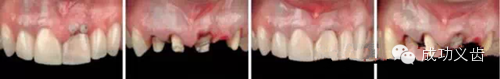

图5.Nobel Replace种植前。联合正畸治疗,以常用的Nobel Replace系统,来修复这个病例。

图6.Nobel Replace种植后。可见缺失的双侧切牙好像从牙龈里生长出来的一样。漂亮的外科、精心的软组织维护、极致的修复、和完善的口内摄影,成就了这个完美的病例。